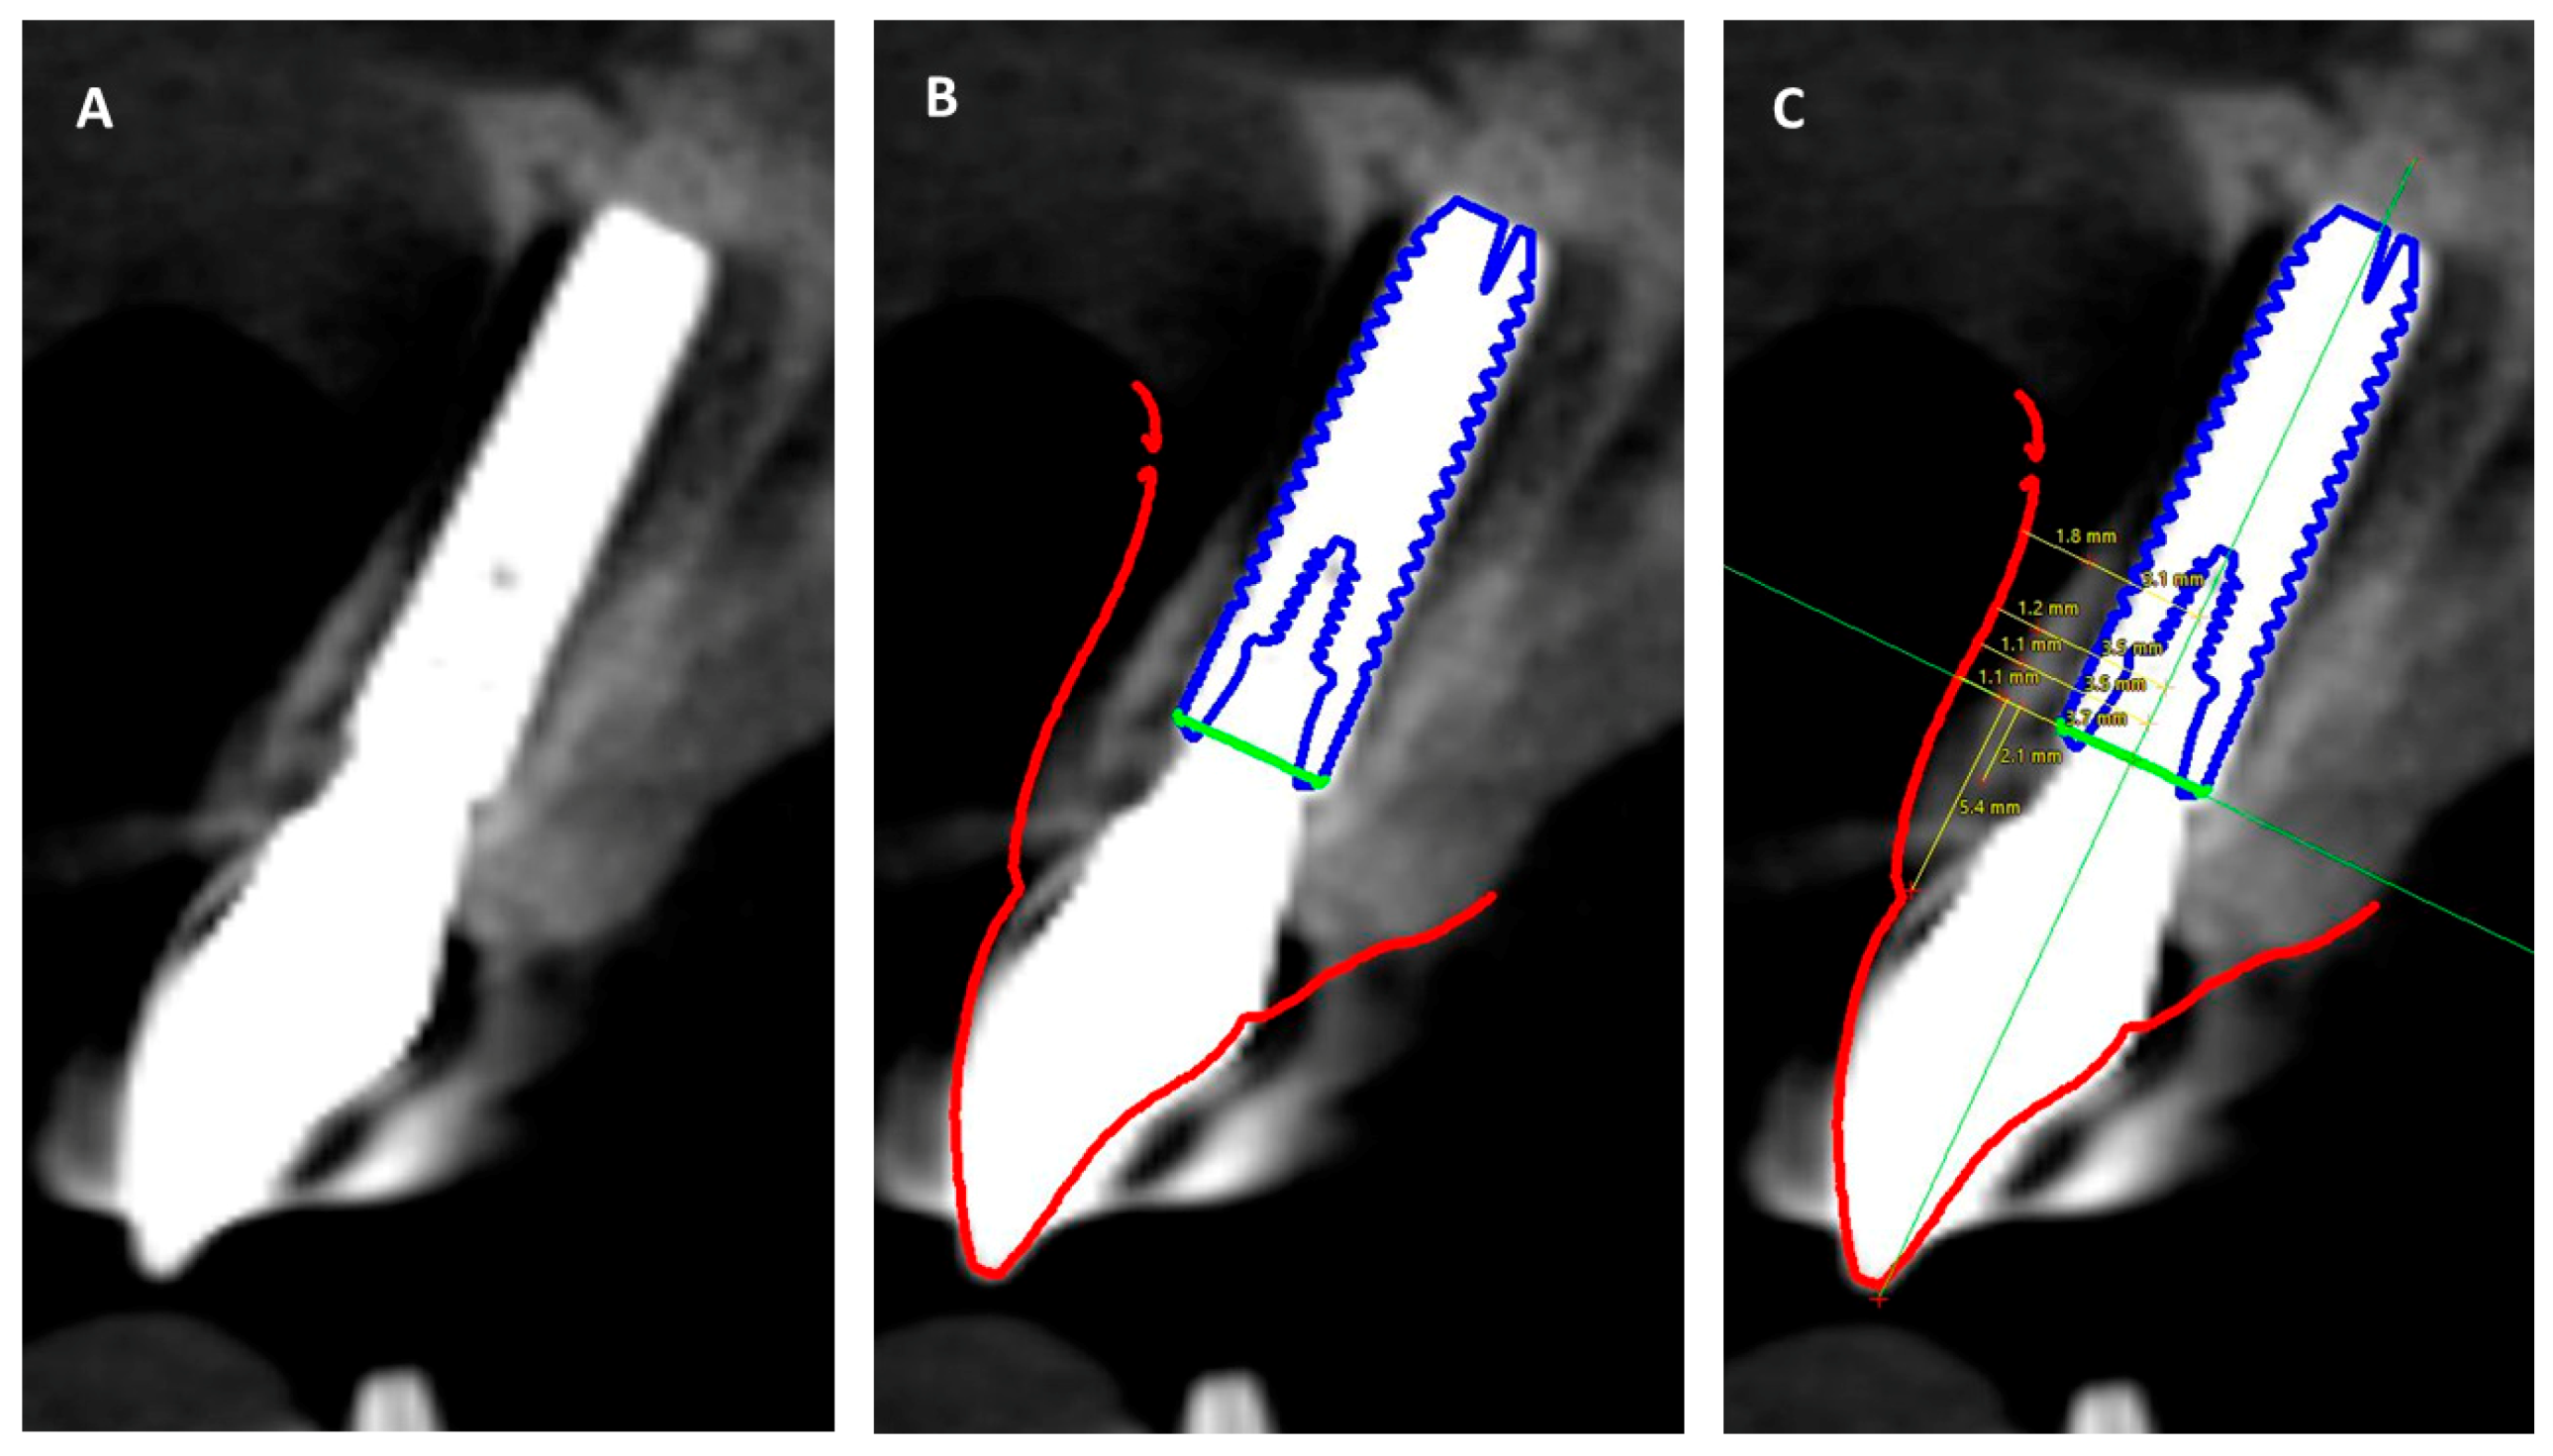

At the 10-year follow-up (T5), a CBCT scan as well as an intraoral digital scan (TRIOS, 3Shape, Copenhagen, Denmark) were done to evaluate the soft and hard tissues around the implant. Both scans were imported into an implant planning software (coDiagnostiX, Dental Wings, Montreal, QC, Canada). The intraoral scan was merged with the DICOM data from the CBCT in the software to evaluate the dimensions of the bone and soft tissues around the implant (Figure 4). After merging the intraoral and CBCT data in the software, an implant avatar with make and dimensions similar to the actual implant was imported and superimposed (Figure 5B). Two annotation lines were drawn through the center of the implant longitudinally and the implant platform horizontally. Horizontal measurements were made from the center of the implant to the outer level of bone and soft tissue at 1, 3, and 5 mm from the implant platform. Vertical measurements were made from the annotation line at the level of the implant platform to evaluate the height of the bone and soft tissue level above the implant (Figure 5C).

Figure 5.

Implant in cross-section view in coDiagnostiX software. (A) Cross-section through the center of the implant, (B) Implant avatar and soft tissue silhouette superimposed on the implant, (C) Vertical and horizontal measurements made using annotation lines to evaluate the thickness and height of soft and hard tissues.

The results from the CBCT and intraoral scan superimposition were interpreted from the midfacial cross-section of the implant (Figure 5). The facial bone extended 2.1 mm above the implant shoulder in a coronal direction and the height of the soft tissue was 5.4 mm when measured from the implant shoulder. The mean thickness of facial bone and soft tissue around the implant was 1.45 and 1.3 mm, respectively (Table 2).